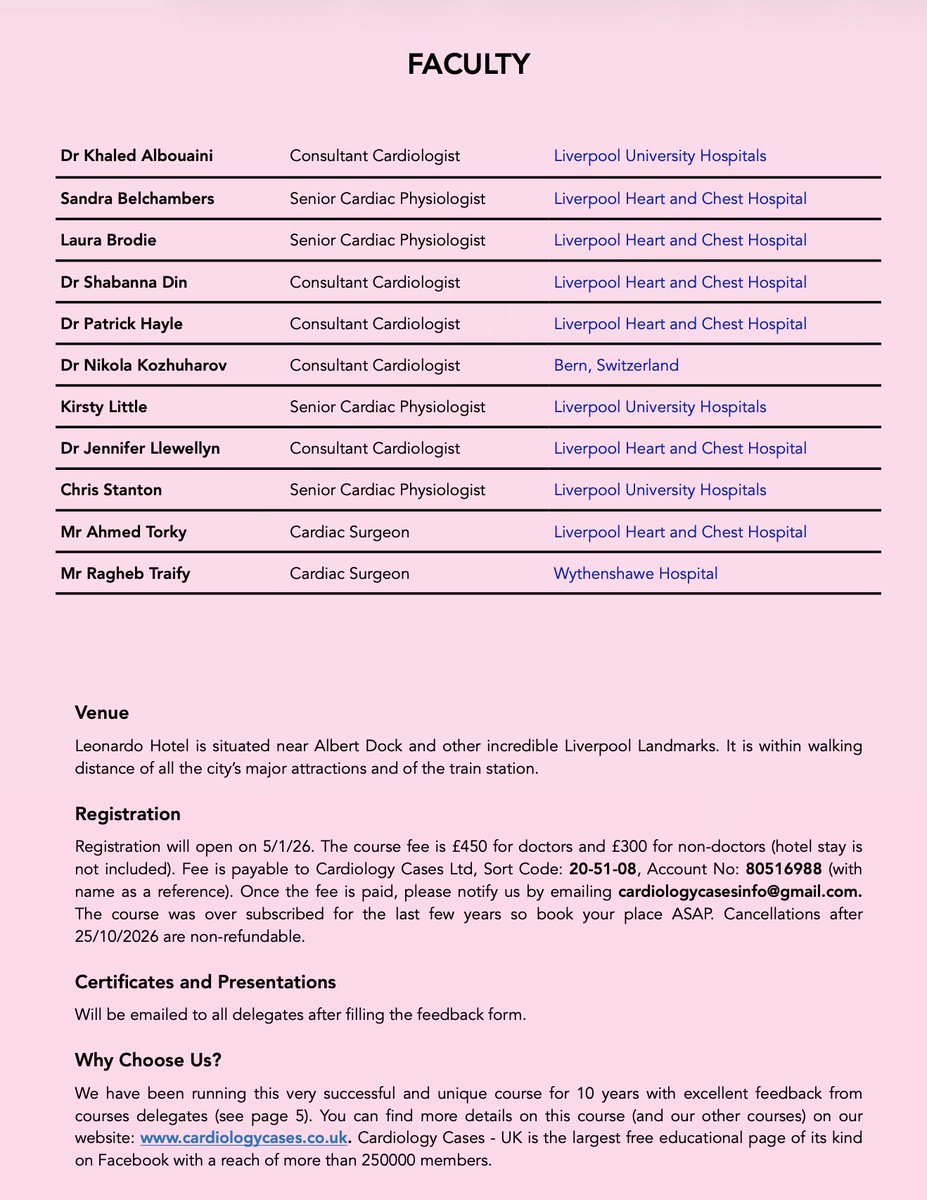

The 14th edition of our National Hands-on Cardiac Pacing Course, scheduled for Thursday -Friday 26-27/11/26. See the overwhelmingly positive feedback (pages 5-8) on PDF flyer: cardiologycases.co.uk. #MedTwitter @BritishCardioSo @TheBJCA @BHRSociety #CardioEd #CardioTwitter